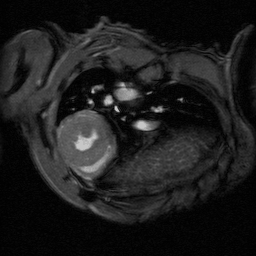

The ultra-high field of the BioSpec 152/11 provides extreme sensitivity for greatest resolution. Its streamlined design for mice studies makes handling simple, while its powerful software guarantees best results. It can be equipped with the MRI CryoProbe to increase sensitivity even further and together with the gradient strength of up to 1000 mT/m, highest resolution is achieved. It is built with nitrogen-free Ultra Shielded and helium Refrigerated (US/R) magnet technology for long service intervals

• Crisp and highly resolved images with native gradient strength of 740 mT/m, upgradable to 1000 mT/m

• MRI CryoProbe for exceptional increase in sensitivity

• MRI sequence portfolio of more than 1,000 sequence variations, including wireless cardiac imaging using navigator based IntraGate methods with cartesian or radial readout, as well as short echo time imaging, such as UTE and ZTE